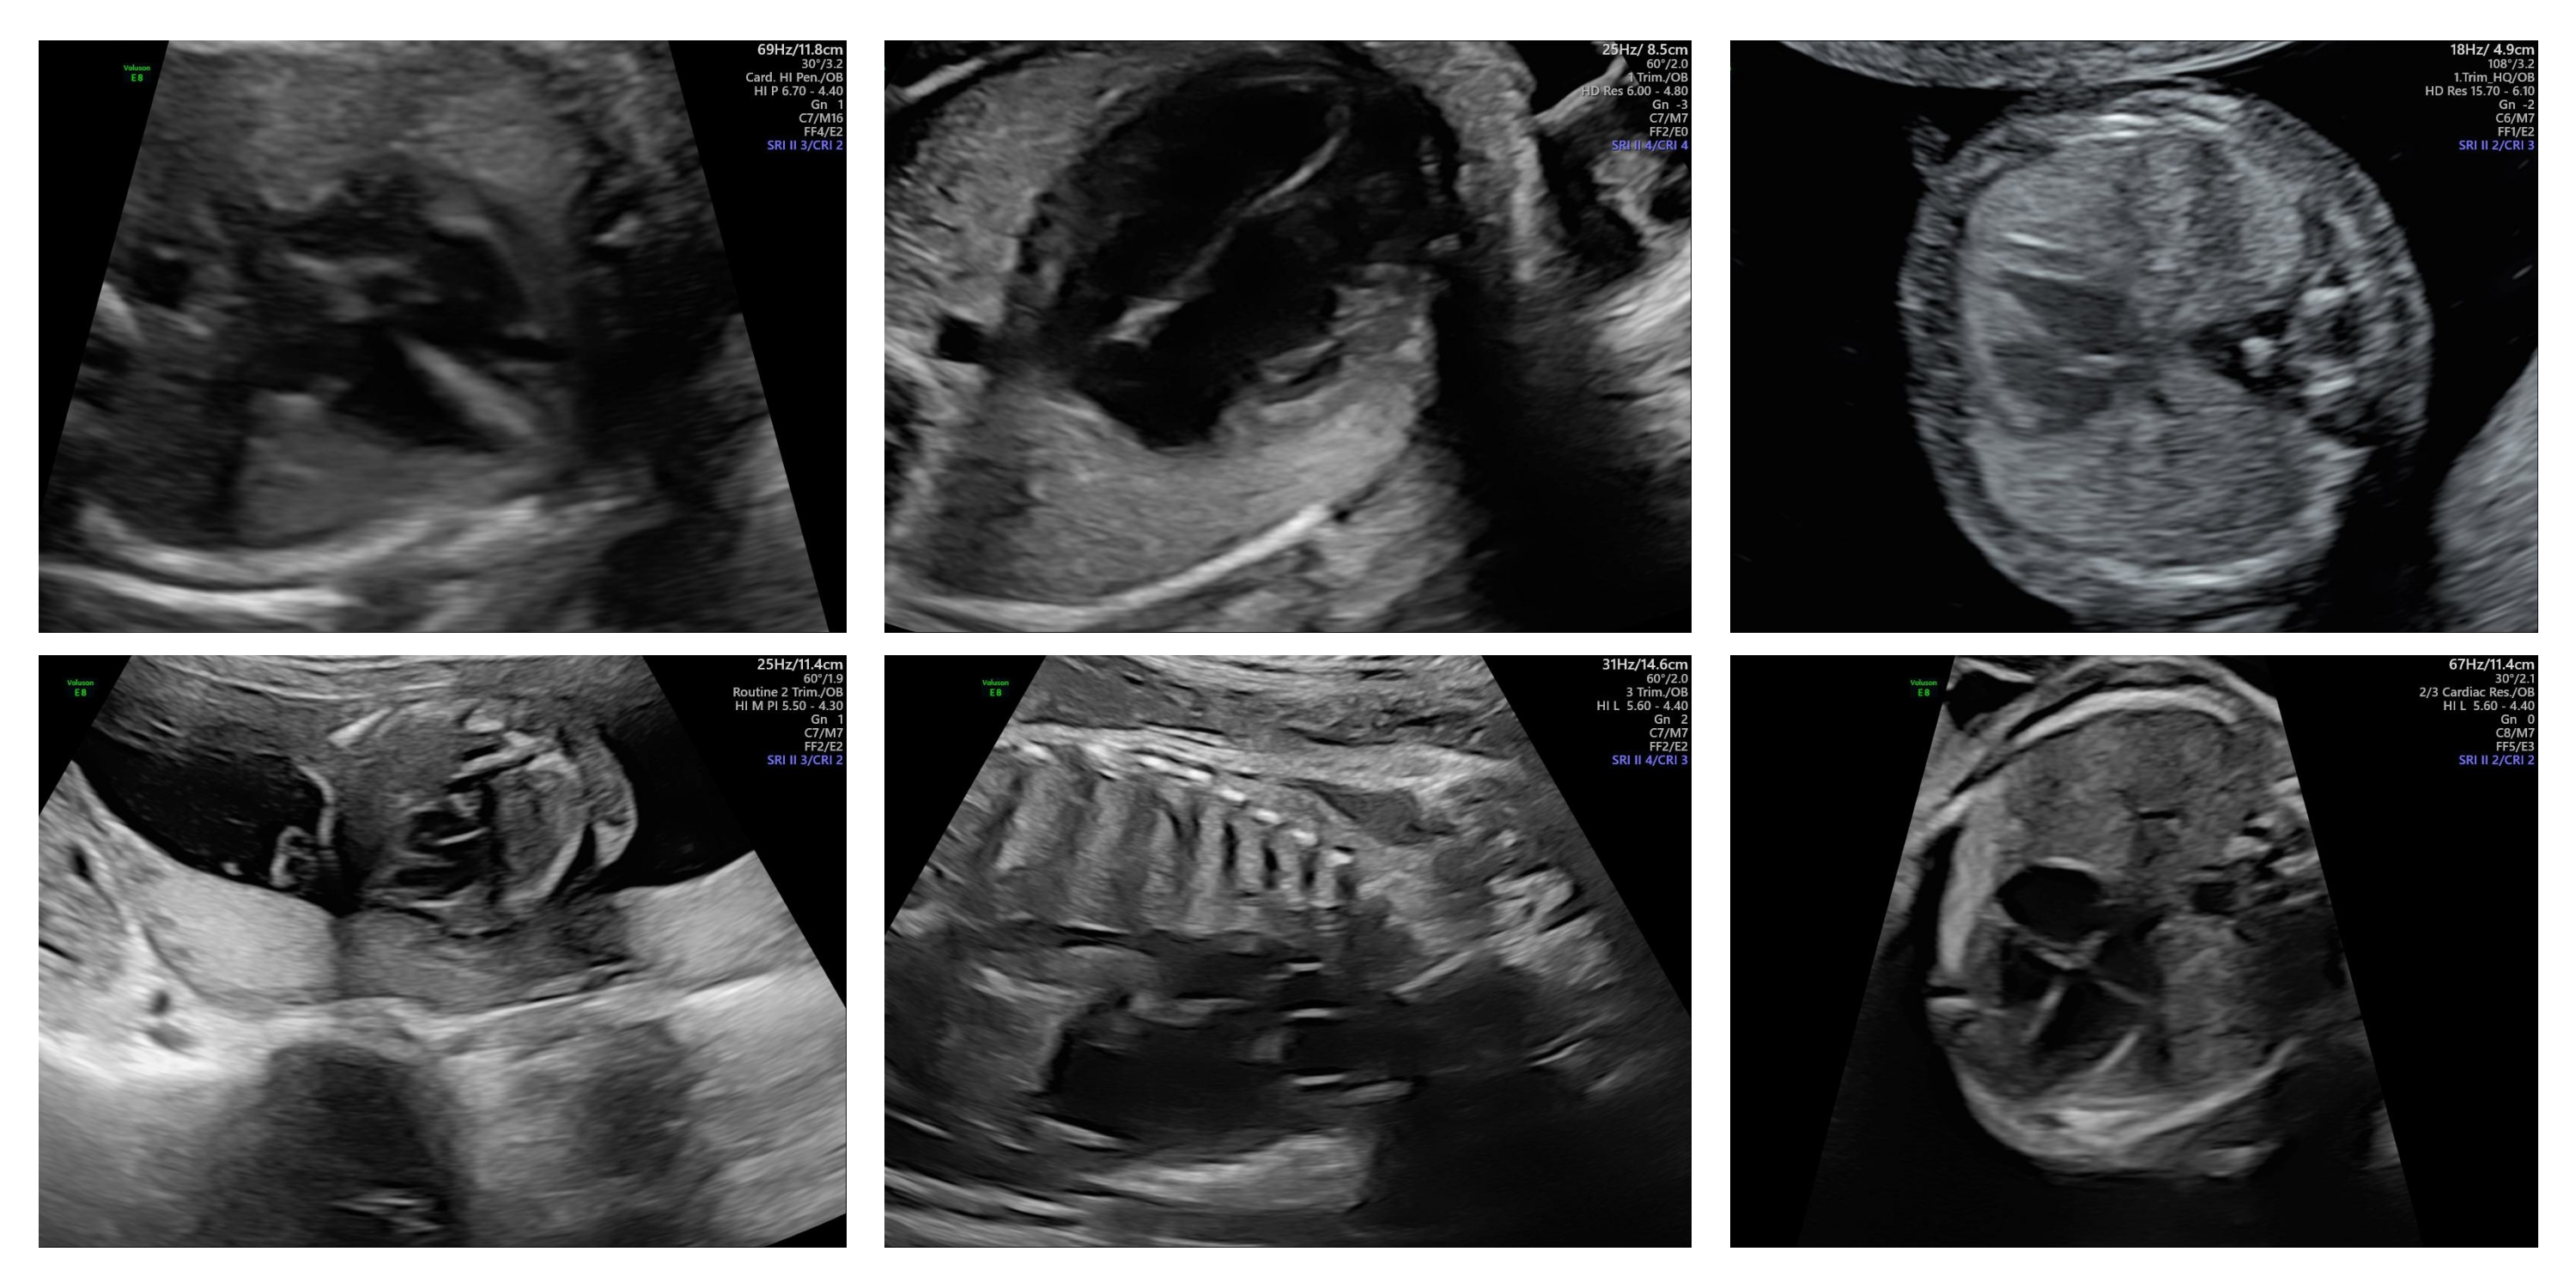

Visual Examples

Here we present a collage of six representative ultrasound images from the CARDIUM dataset.